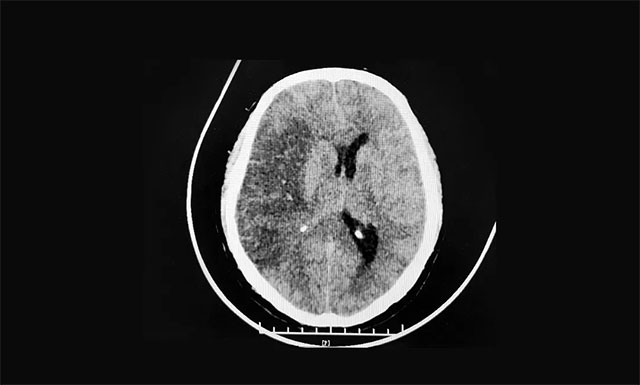

▲ 大面积出血性脑梗死

CT显示,右侧额颞顶枕叶(大脑中动脉供血区)大面积出血性脑梗死,脑肿胀,右侧高颅压。蛛网膜下腔出血。针对患者病情,脑血管病病区主任张琪博士迅速在急诊下为患者行右侧颅骨去骨瓣减压术,术后患者病情逐渐平稳。